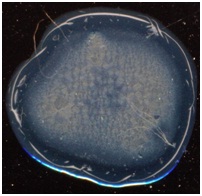

окрашенных тезиограмм плазмы крови больных гломерулонефритом были обнаружены

довольно разрозненные картины, не позволяющие выделить четкие морфотипы (рис1).

Рисунок 1.

Окрашенные амидочерным 10В тезиограммы плазмы крови больных гломерулонефритом.

Среди

окрашенных тезиограмм плазм крови больных гломерулонефритом можно было выделить

следующие общие признаки:

1)

Можно

выделить 3-4 концентрические зоны – краевая, центральная и промежуточная,

состоящая из двух подзон.

2)

Отсутствовали

радиальные трещины и центральная точка растрескивания.

3)

конкреции в центральной зоне фации.

4)

В

большинстве случаев в центральной зоне наблюдались кристаллические структуры

5)

Наблюдалось

незначительное увеличение краевой зоны.

6)

большинстве случаев в краевой зоне имелись конкреции, заполняющие всю площадь

сектора.